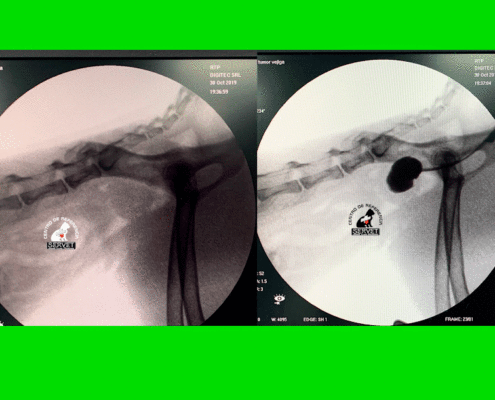

Fluoroscópia

Útil en una amplia gama de procedimientos tanto vasculares como respiratorios para el diagnóstico. Un gran apoyo en cirugía vascular y traumatología y neurocirugía al permitir ver en tiempo real (video) imágenes radiológicas en la mesa del quirófano.